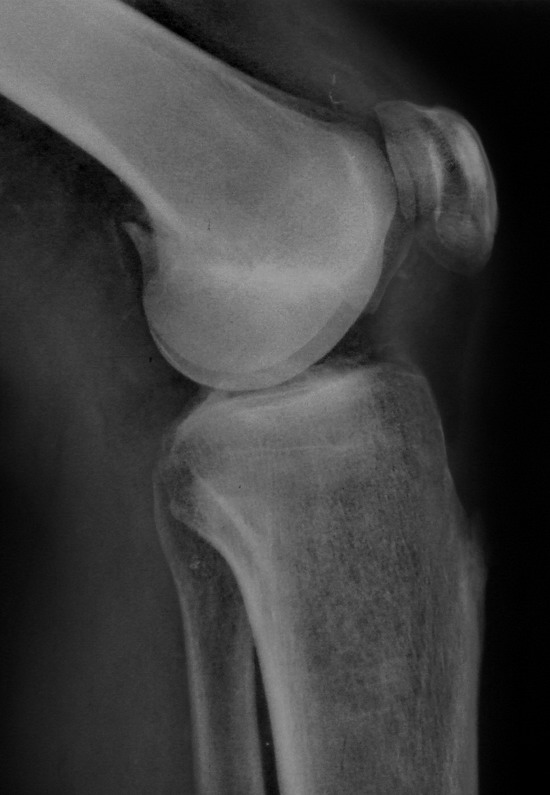

По одной проекции конечно сложно представить себе ситуацию во всех подробностях. Но первое, что приходит в голову, учитывая молодой возраст, хорошую функцию сустава и достаточно ровную линию перелома - открытая репозиция с фиксацией отломков мощными компрессирующими винтами.

Около двух лет назад оперировали подобный перелом у женщины лет 45, с момента травмы до обращения к нам прошло около 1,5 месяцев. Выполнили открытую репозицию, остеосинтез компрессирующими спонгиозными винтами. Во время операции столкнулись с проблемой: так как задний фрагмент сместился вверх, а его суставная поверхность основная нагружаемая часть мыщелка, то вся нагрузка по оси пришлась на суставную поверхность переднего отломка и возник импрессионный перелом с вдавлением ло 1 см по высоте. После элевации хряща и сухондральной кости пришлось делать костную пластику.Результат и рентгенологический и функциональный через 6 мес был хороший. Если найду Р-граммы выложу

“Перелом наружного мыщелка правого бедра во фрональной плоскости был не замечен”

При изолированных переломах можно лечить миниинвазивно каннюлированными винтами, но в большинстве Hoffa компонент сопровождается другими типами перелома дистального бедра. Выбор доступа зависит от расположения фрагментов и большинстве латеральный субвастус доступ подойдет для фиксации перелома.

В данном случае предпочтителен парапателлярный доступ, где необходимо создать лучший обзор к мыщелку. После остеотомии и репозиции фиксацию надо проделать поперечными винтами и дополнительно задней antiglade plate - сделанной из 1/3 tubular plate.

Спасибо большое за советы! Добавляю некоторые КТ снимки. Перелом коллеги не диагностировали, видимо, расценив костную травму как повреждение задне-латерального комплекса коленного сустава. Отпишусь по результату выполненной операции.